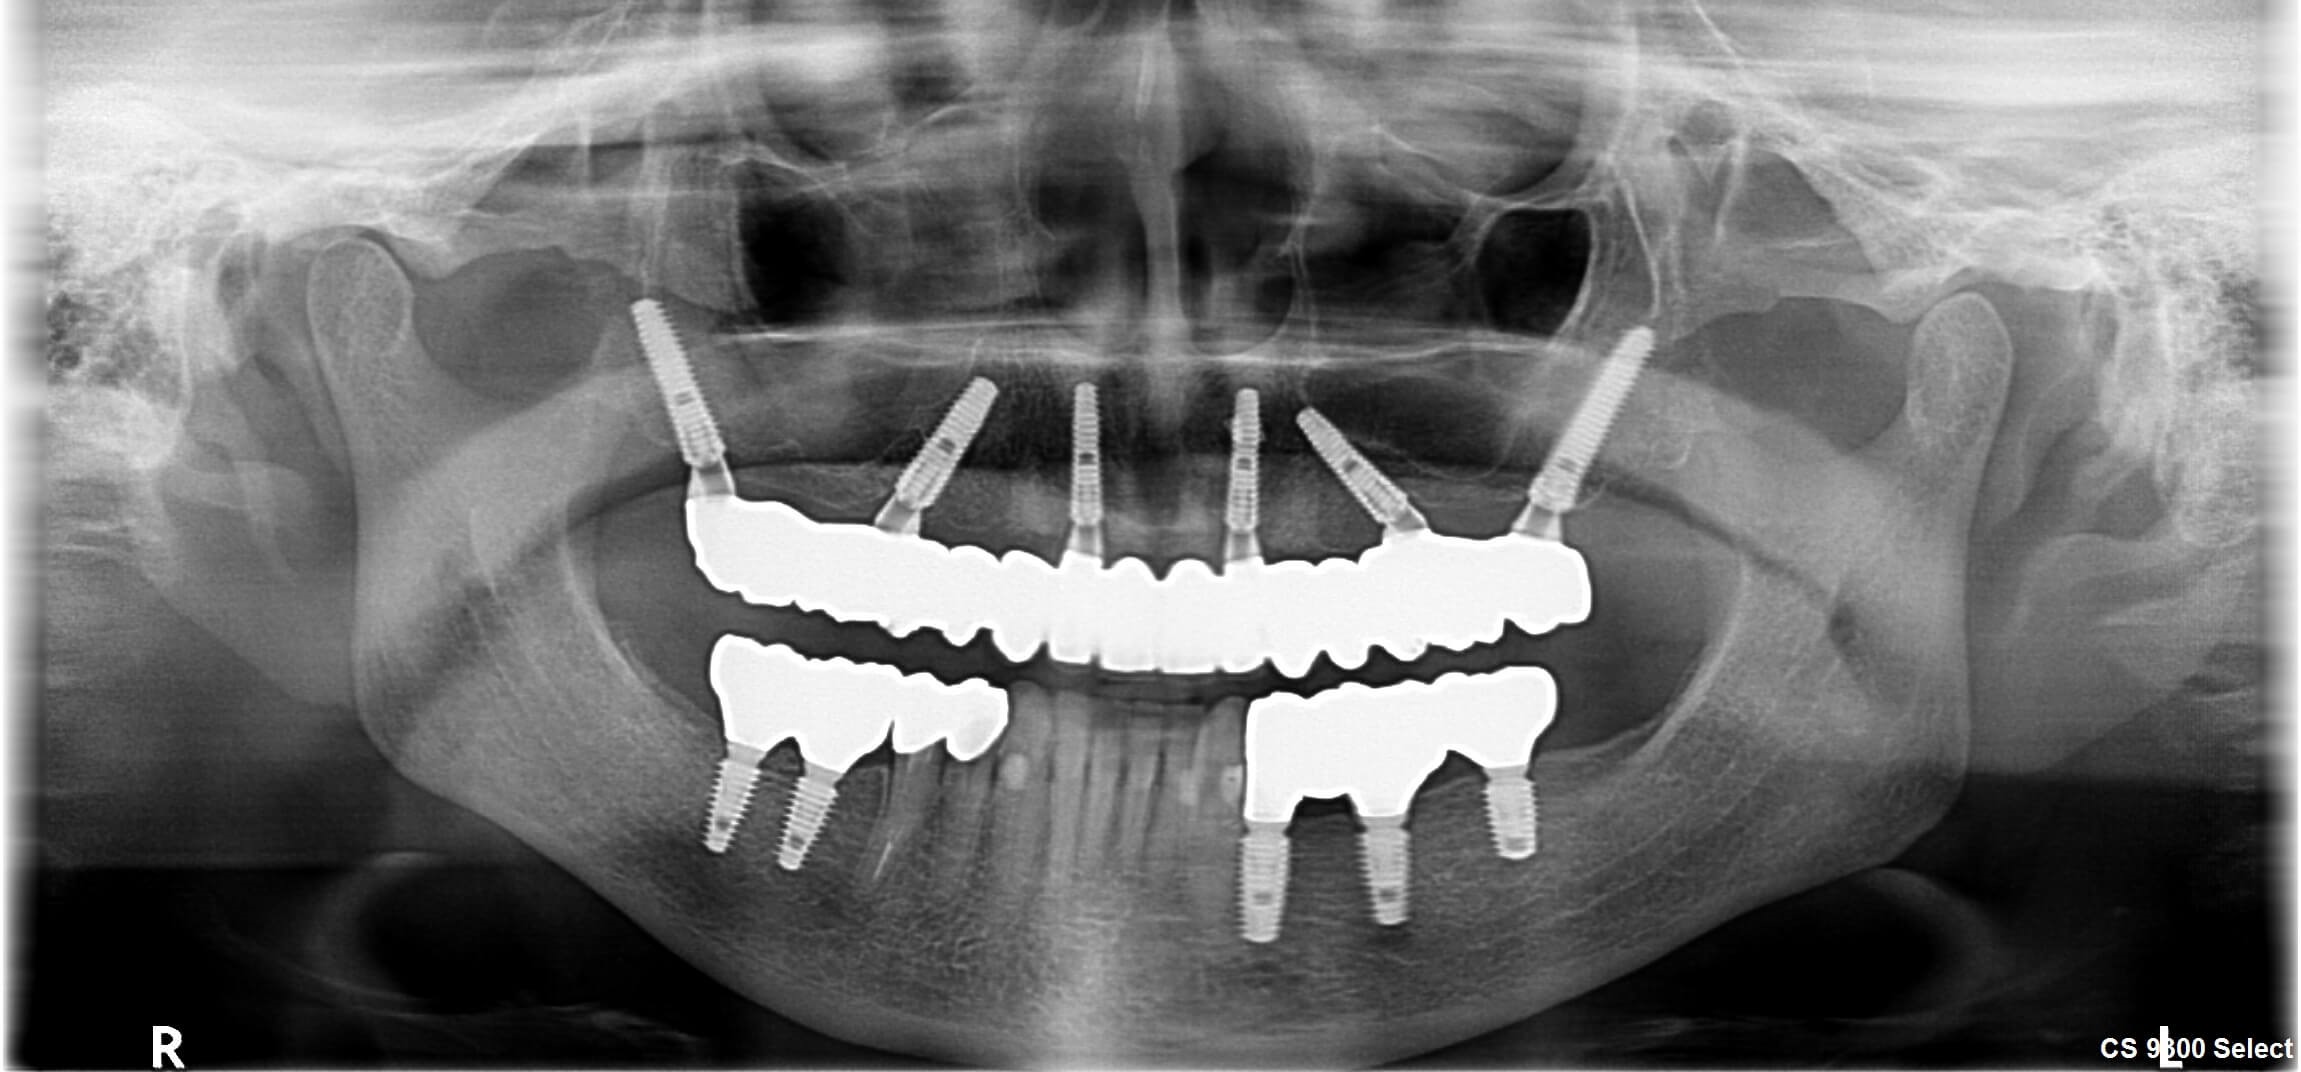

Пациент приехала к нам в клинику для полного восстановления зубов. На верхней челюсти у нее оставалось всего 6 зубов, после снятия коронок с них выяснилось, что они идут под удаление. В боковых отделах зубов не было давно. Со слов пациента, ранее ей проводились операции на обеих верхнечелюстных пазухах. На снимках мы видели подтверждение ее слов, на наружных стенках пазух были обнаружены дефекты. Это делало невозможным проведения стандартных процедур по наращиванию костной ткани в боковых отделах и классическую имплантацию. В таких случаях мы можем провести имплантацию по методике All-On-6 (“все на шести”), при которой имплантаты устанавливаются в свод верхнечелюстных пазух под определенными углами.

В ее случае мы использовали модифицированную методику “All-On-6”, установив всего 6 имплантатов под углом на верхней челюсти и изготовив временный протез максимально похожий на ее собственные зубы: сформировали профили прорезывания в области каждого зуба, чтобы получить максимальный эстетический результат. Первый этап лечения на этом закончился.